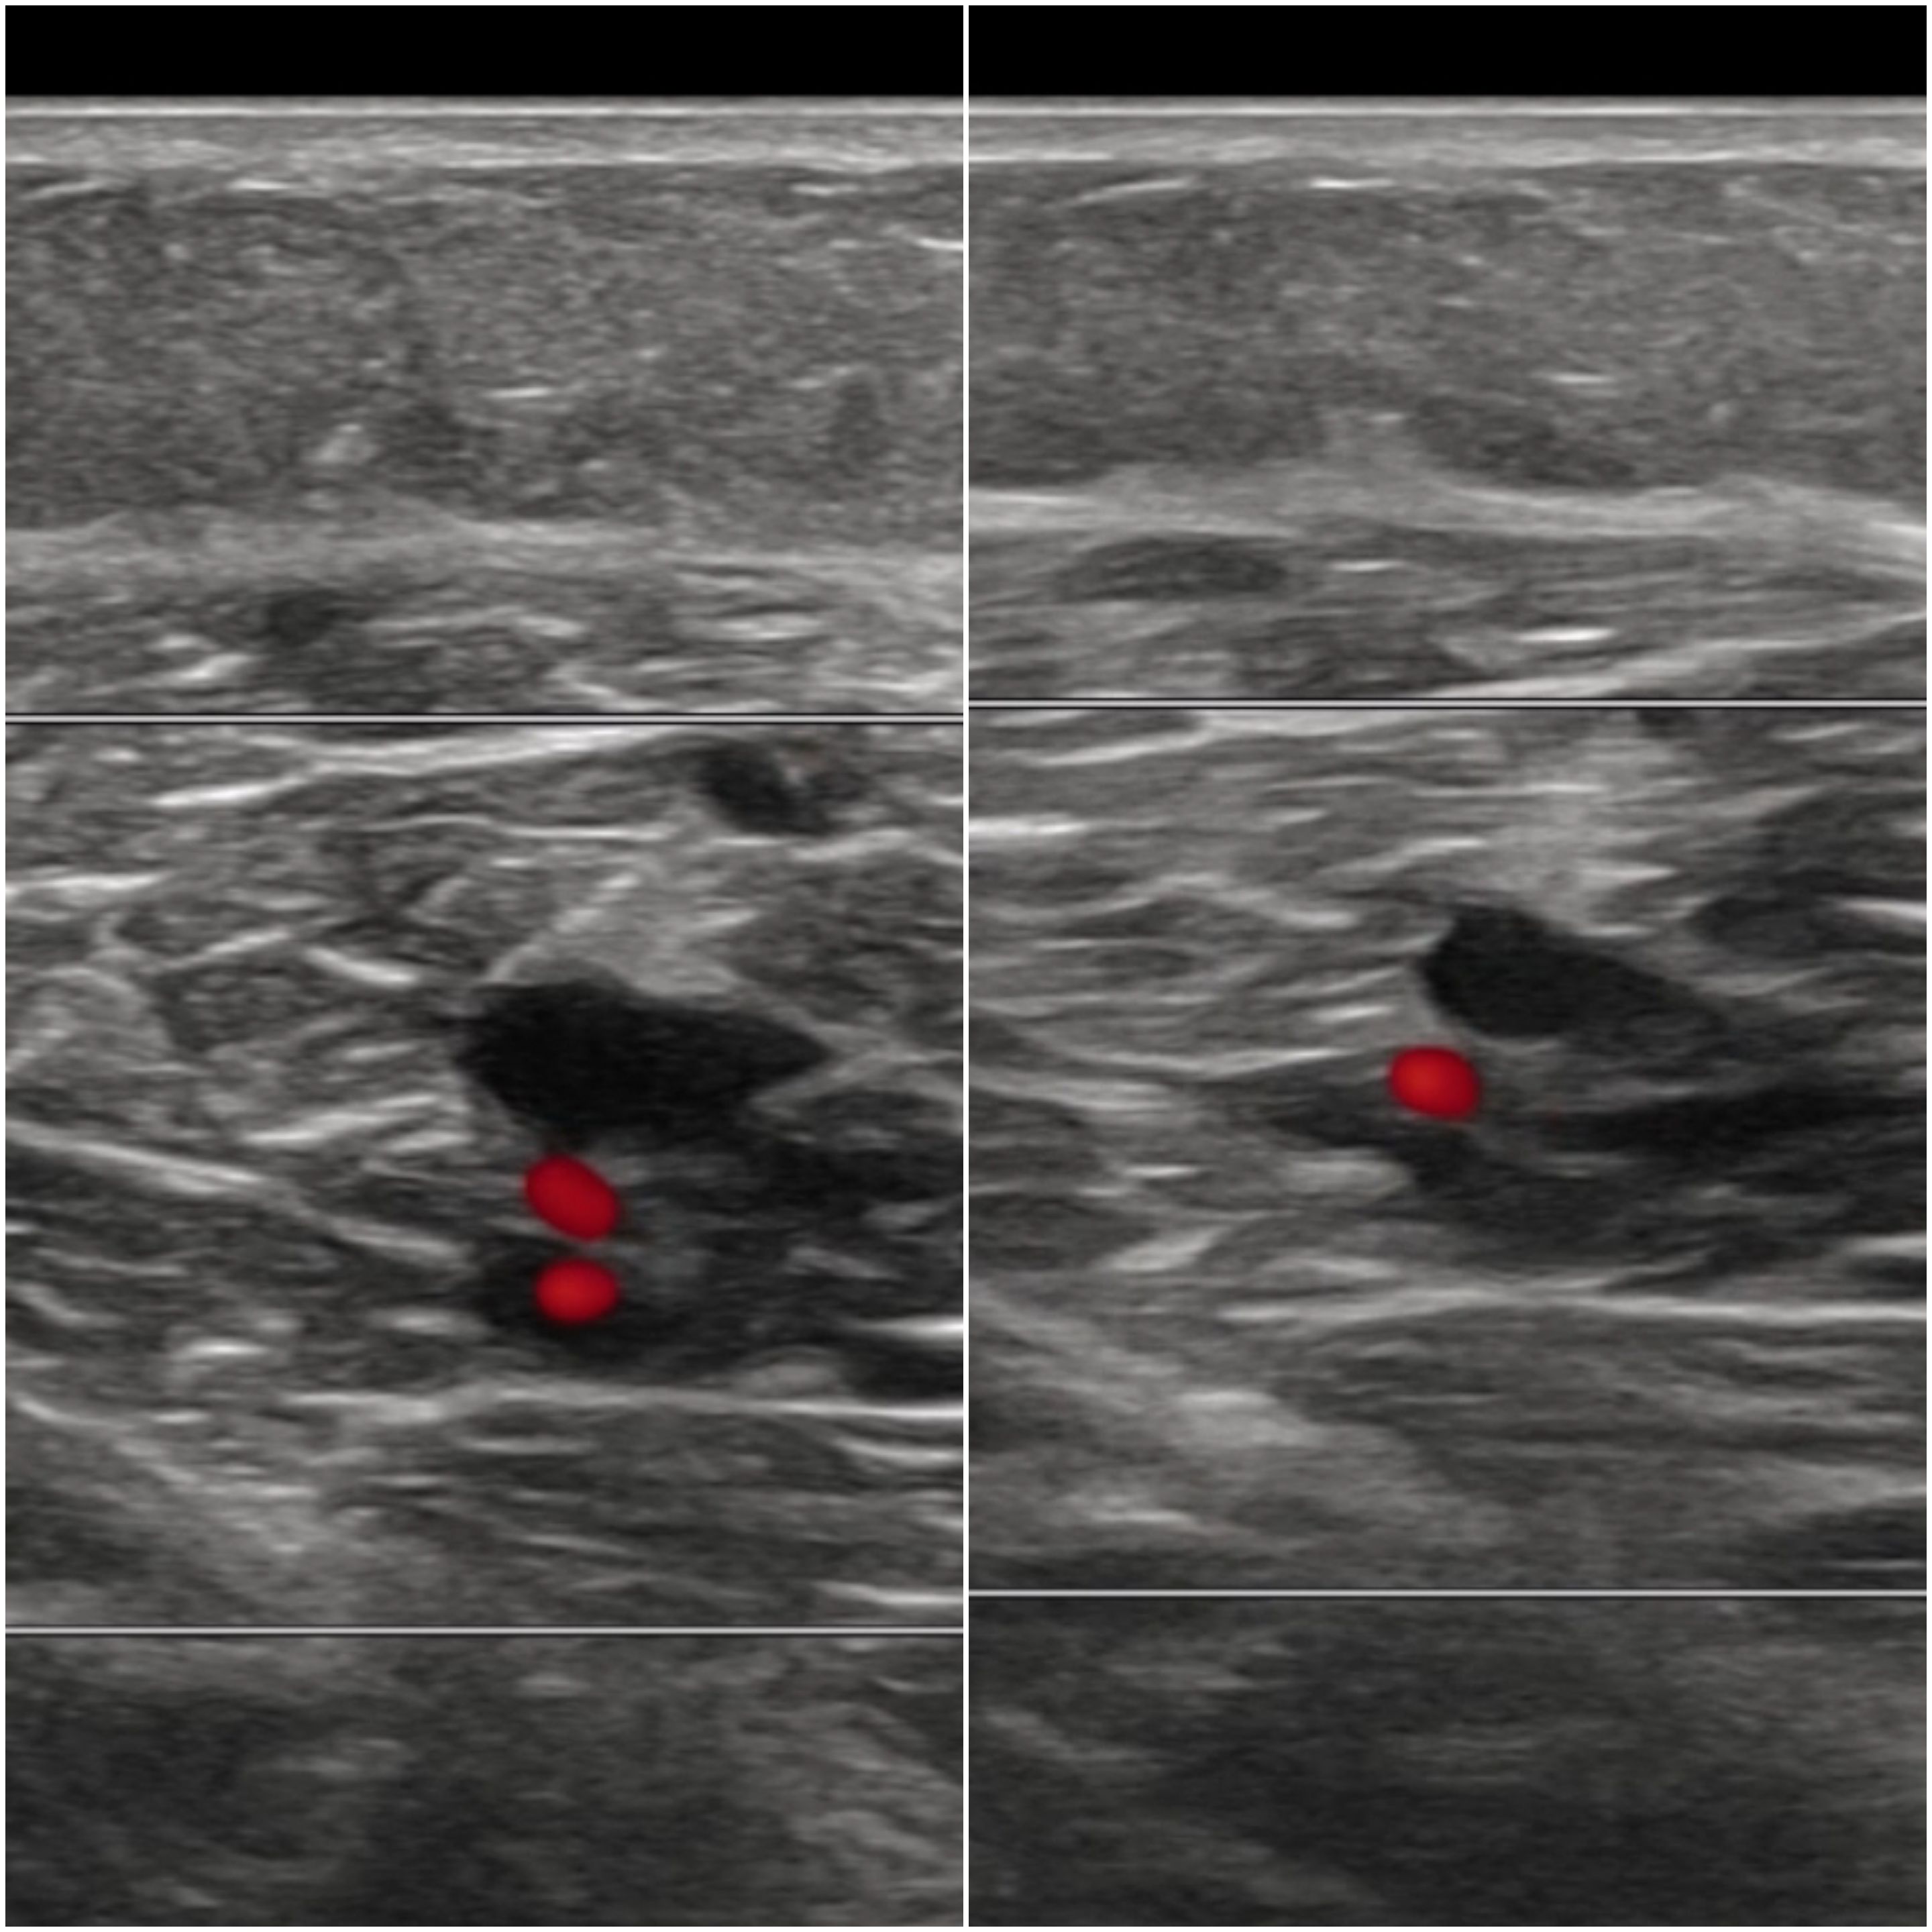

Ecografía clínica: no compresibilidad venosa, con signo de «oleada» negativo en venas tibiales posteriores.

Debemos conocer los signos ecográficos de la trombosis venosa: ausencia de flujo venoso, no compresibilidad, «oleada» negativo, material ecogénico intraluminal según la fase en la que esté y sin captación Doppler pulsado. En caso de tromboflebitis la localización será superficial. La rotura de fibras con clínica de dolor súbito como «una pedrada». La rotura de un quiste de Baker en cara posterior de la rodilla.